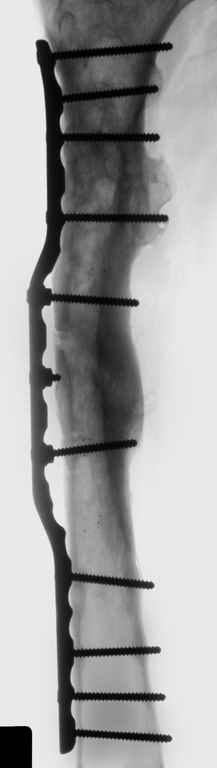

Leonid Pollyak 02 Январь 2005, 22:42

Хотелось бы показать, что получилось в результате.

Операция выполнялась с помощью А.Н.Челнокова. Очень понравилась технология выполнения блокируемого остеосинтеза с использованием спицевого дистрактора, модифицированный гвоздь с латерализованным проксимальным отделом и возможностью многовинтовой фиксации проксимального и дистального участков бедра.

Моё мнение, что двойная остеотомия бедра с аппаратом Илизарова + Гексаподный механизм, или Тэйлора, В данной ситуации является методом выбора. Я очень извеняюсь за качество прилагаемых снимков, в которых я постарался отразить разницу междe одной и двумя остеотомиями бедра.